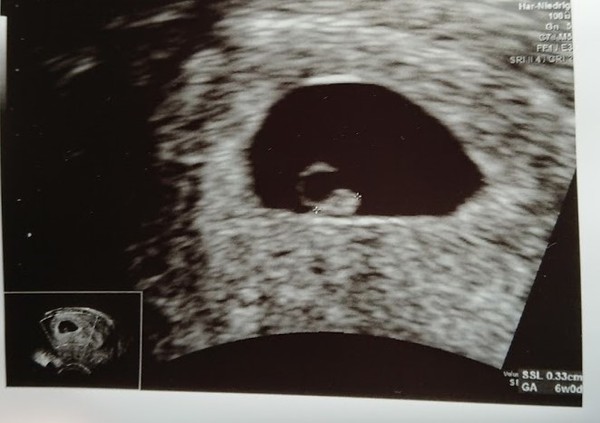

PurplePansy05 · 21/12/2020 16:11

Apologies for any scan-related triggers

Here is our little rainbow baby Purple at 6+2 🌈 xxx